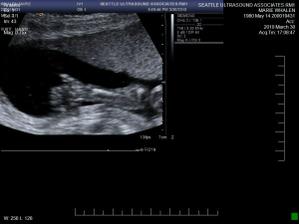

• 30.3. 2010 dalsi ultrazvuk v druhem trimestru odhalil zdrave miminko - je to chlapecek 🙂